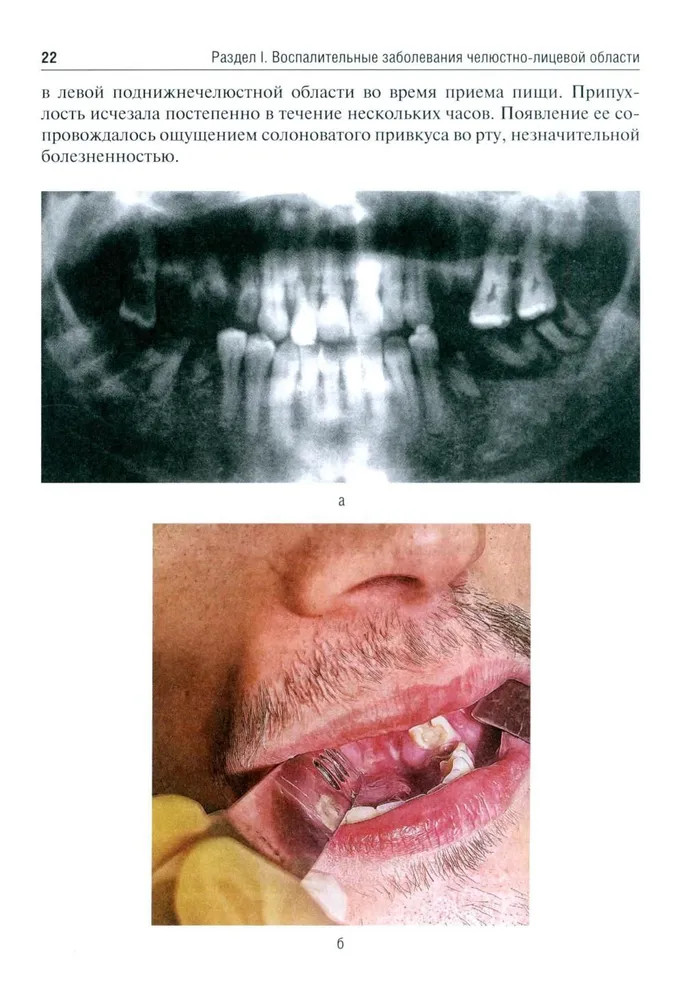

💳 Оплатить за товар можно при получении 🇰🇿 Есть бесплатная доставка по Казахстану от 1 дня 🎁 Копите бонусы с каждой покупки Учебное пособие подготовлено для студентов стоматологических факультетов медицинских вузов в соответствии с требованиями государственного образовательного стандарта и содержит сведения, необходимые для освоения в рамках учебной программы по специальности «Стоматология». В нем представлен набор иллюстрированных задач, в которых приведены наиболее часто встречающиеся клинические ситуации по основным разделам специальности: воспалительные заболевания челюстно-лицевой области (неспецифические и специфические); травматические повреждения и последствия травмы; онкологические заболевания; заболевания слюнных желез; заболевания височно-нижнечелюстного сустава; комплексное обследование и лечение пациентов с врожденными и приобретенными дефектами и деформациями мягких тканей и костей челюстно-лицевой области. Рассмотренные клинические ситуации помогут формированию у студентов профессиональных умений по диагностике и планированию комплексного лечения основных заболеваний челюстно-лицевой области. |